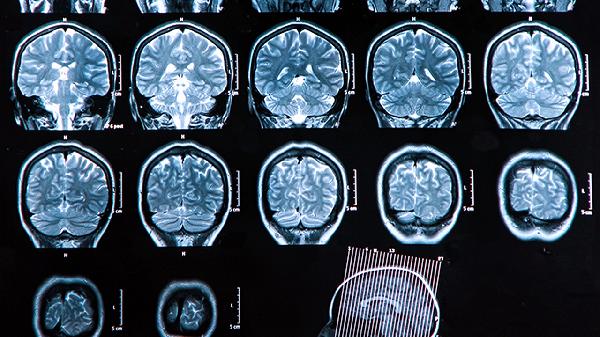

大脑失去记忆可能是由阿尔茨海默病、血管性痴呆、脑外伤、脑炎、短暂性全面遗忘症等疾病引起的。记忆障碍的严重程度和病因相关,需结合具体症状和医学检查明确诊断。

阿尔茨海默病是一种神经退行性疾病,主要表现为进行性记忆减退和认知功能下降。早期症状常为近事遗忘,随着病情发展可能出现定向障碍和语言能力丧失。该病与脑内β-淀粉样蛋白沉积和神经纤维缠结有关,目前尚无根治方法,但可通过多奈哌齐、美金刚、卡巴拉汀等药物延缓病情进展。

血管性痴呆由脑血管病变导致脑组织缺血缺氧引起,记忆障碍多呈阶梯式恶化。患者常伴有高血压、糖尿病等基础疾病,可能出现执行功能障碍和情绪波动。治疗需控制基础疾病,改善脑循环,可使用尼莫地平、丁苯酞、银杏叶提取物等药物。

头部受到外力作用可能导致脑组织损伤,引发逆行性或顺行性遗忘。轻度脑外伤可能仅造成短暂记忆障碍,严重创伤可导致长期认知缺陷。急性期需进行神经外科评估,恢复期可进行认知康复训练,必要时使用神经营养药物如脑蛋白水解物、胞磷胆碱等。

病毒或细菌感染引起的脑炎可能损害海马等记忆相关脑区,导致记忆功能受损。患者除记忆障碍外,常伴有发热、头痛、意识模糊等症状。治疗需针对病原体使用抗病毒或抗生素药物,如阿昔洛韦、更昔洛韦等,严重病例需住院治疗。

短暂性全面遗忘症表现为突发性、短暂性的记忆丧失,通常持续数小时,事后不能回忆发作期间的情况。病因可能与脑血管痉挛或癫痫有关,多数患者可完全恢复。发作期需排除脑血管意外,必要时进行脑电图和影像学检查。